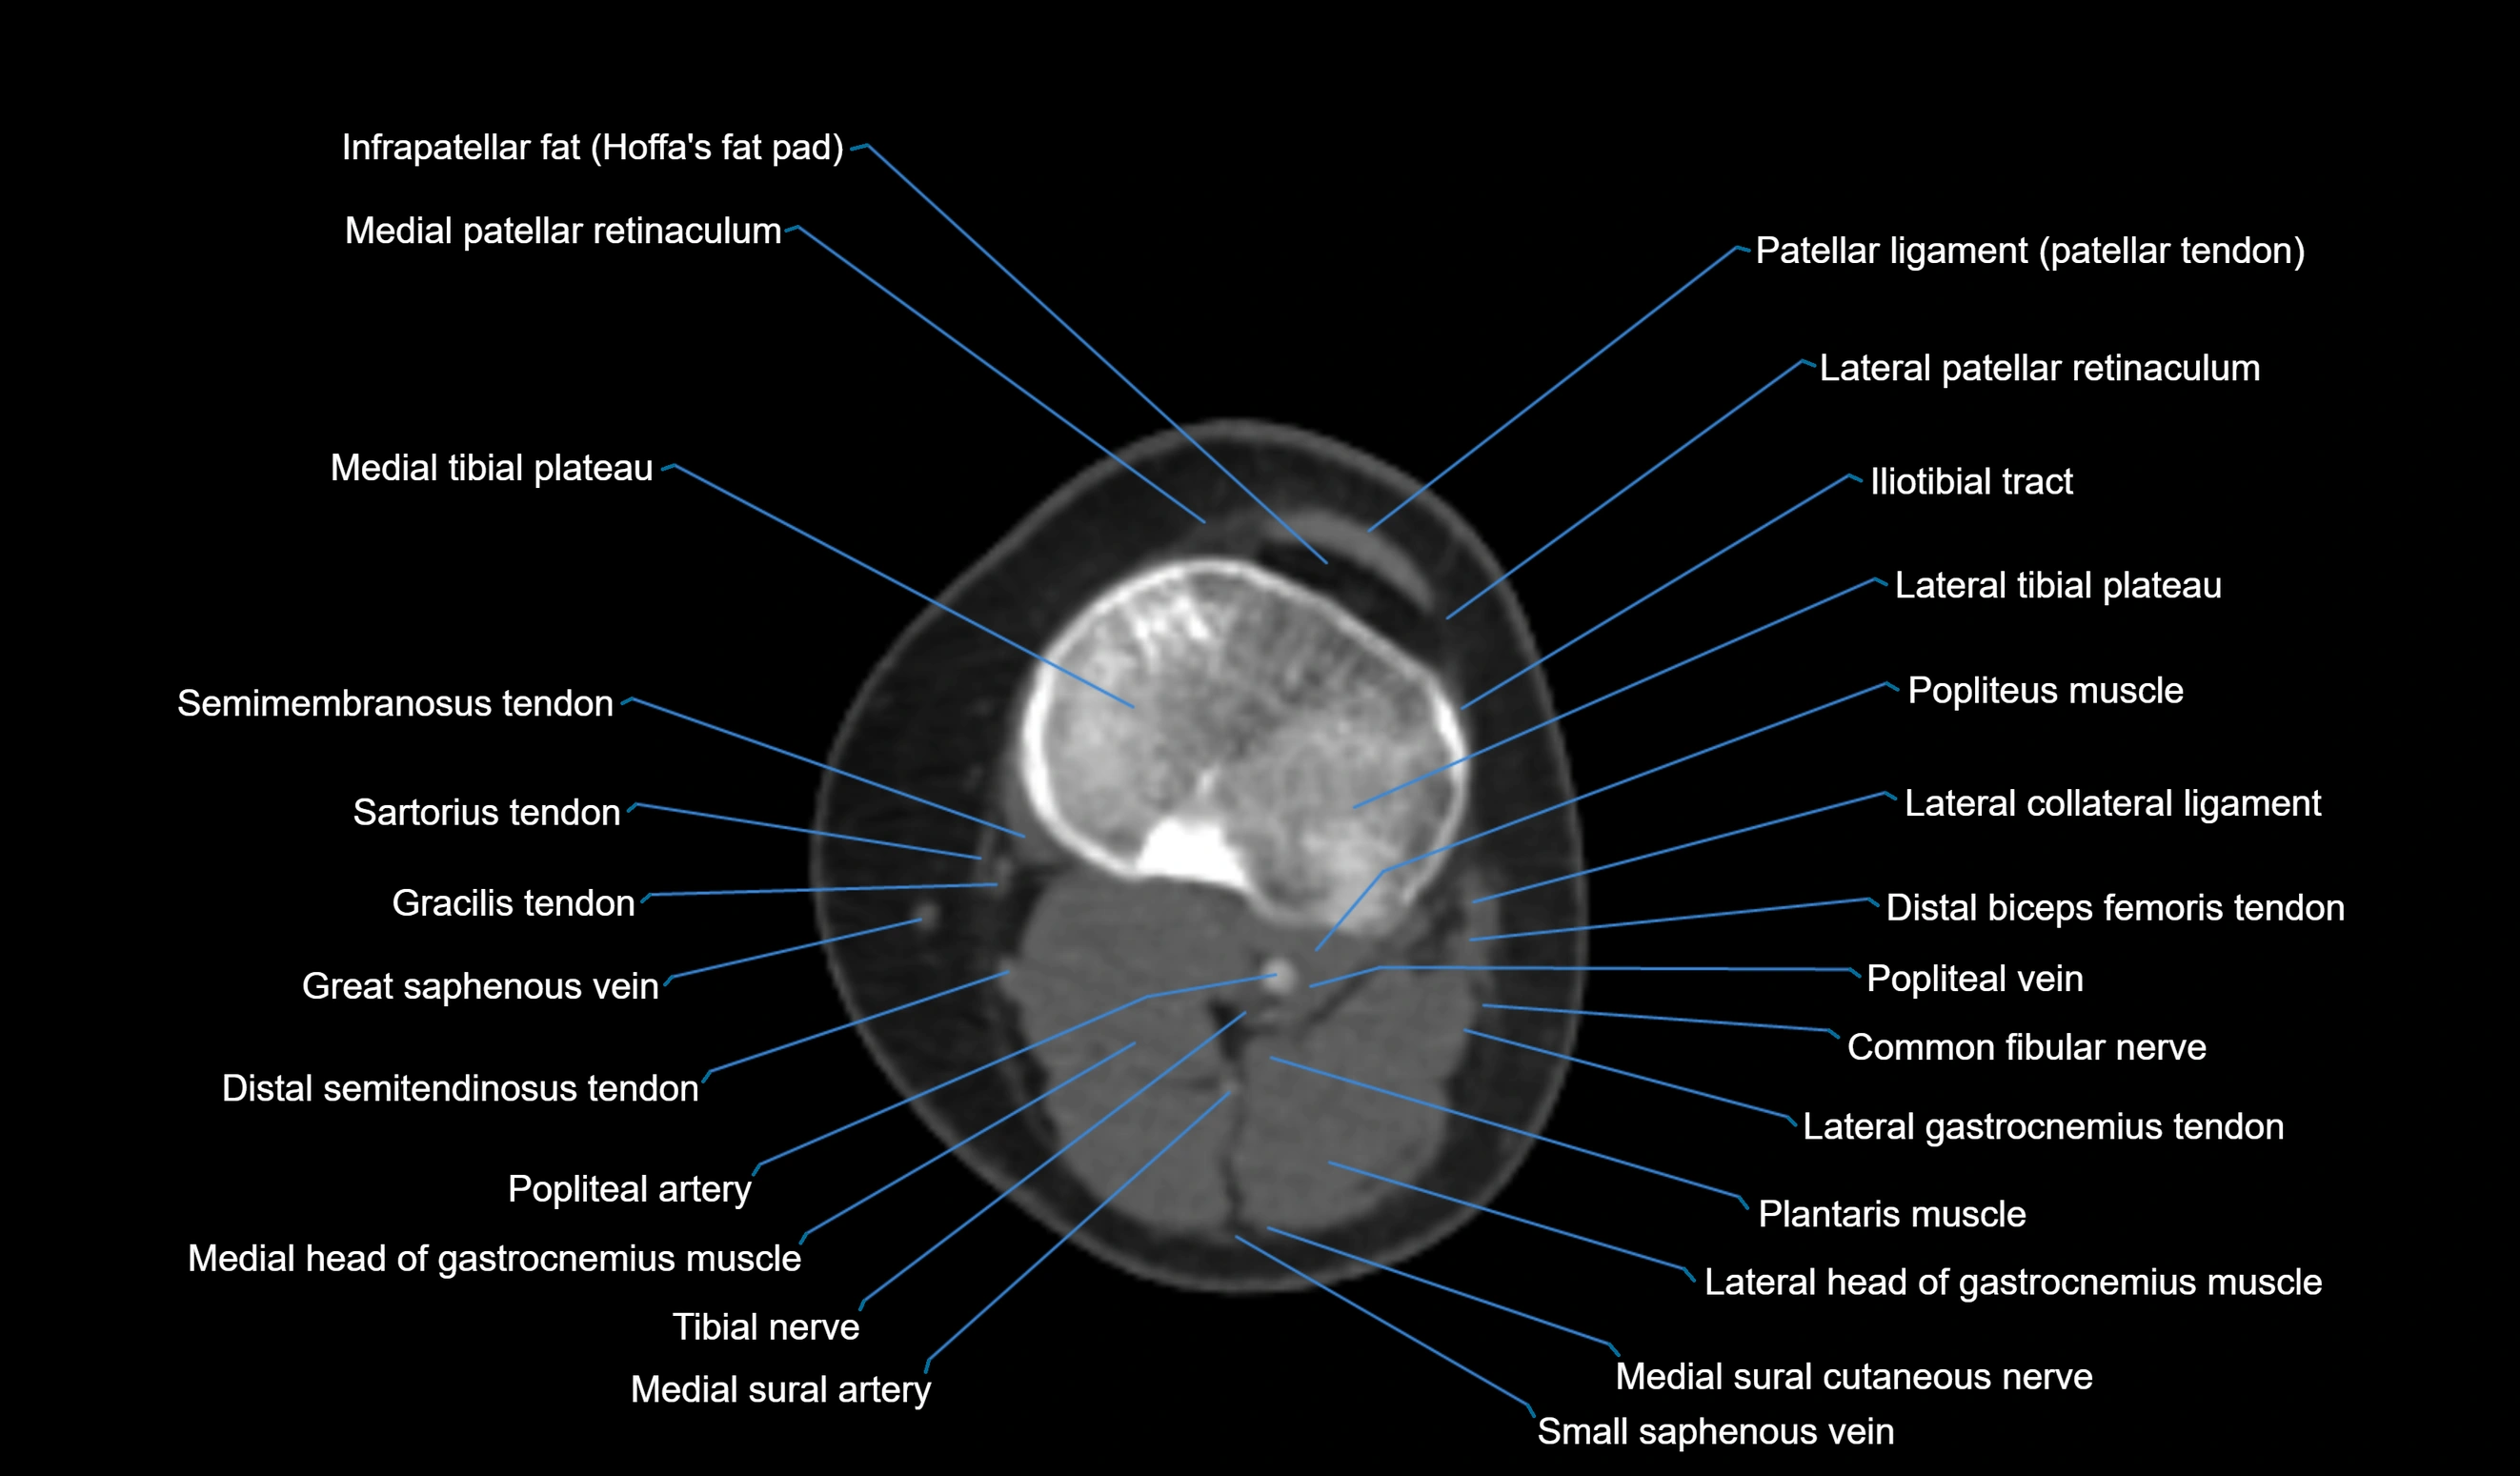

- Common fibular nerve

- Lateral collateral ligament

- Lateral gastrocnemius tendon

- Lateral head of gastrocnemius muscle

- Lateral tibial plateau

- Medial head of gastrocnemius muscle

- Medial patellar retinaculum

- Medial sural cutaneous nerve

- Medial tibial plateau

- Patellar tendon (patellar ligament)

- Popliteal artery

- Popliteal vein

- Popliteus muscle

- Small saphenous vein

- Tibial nerve